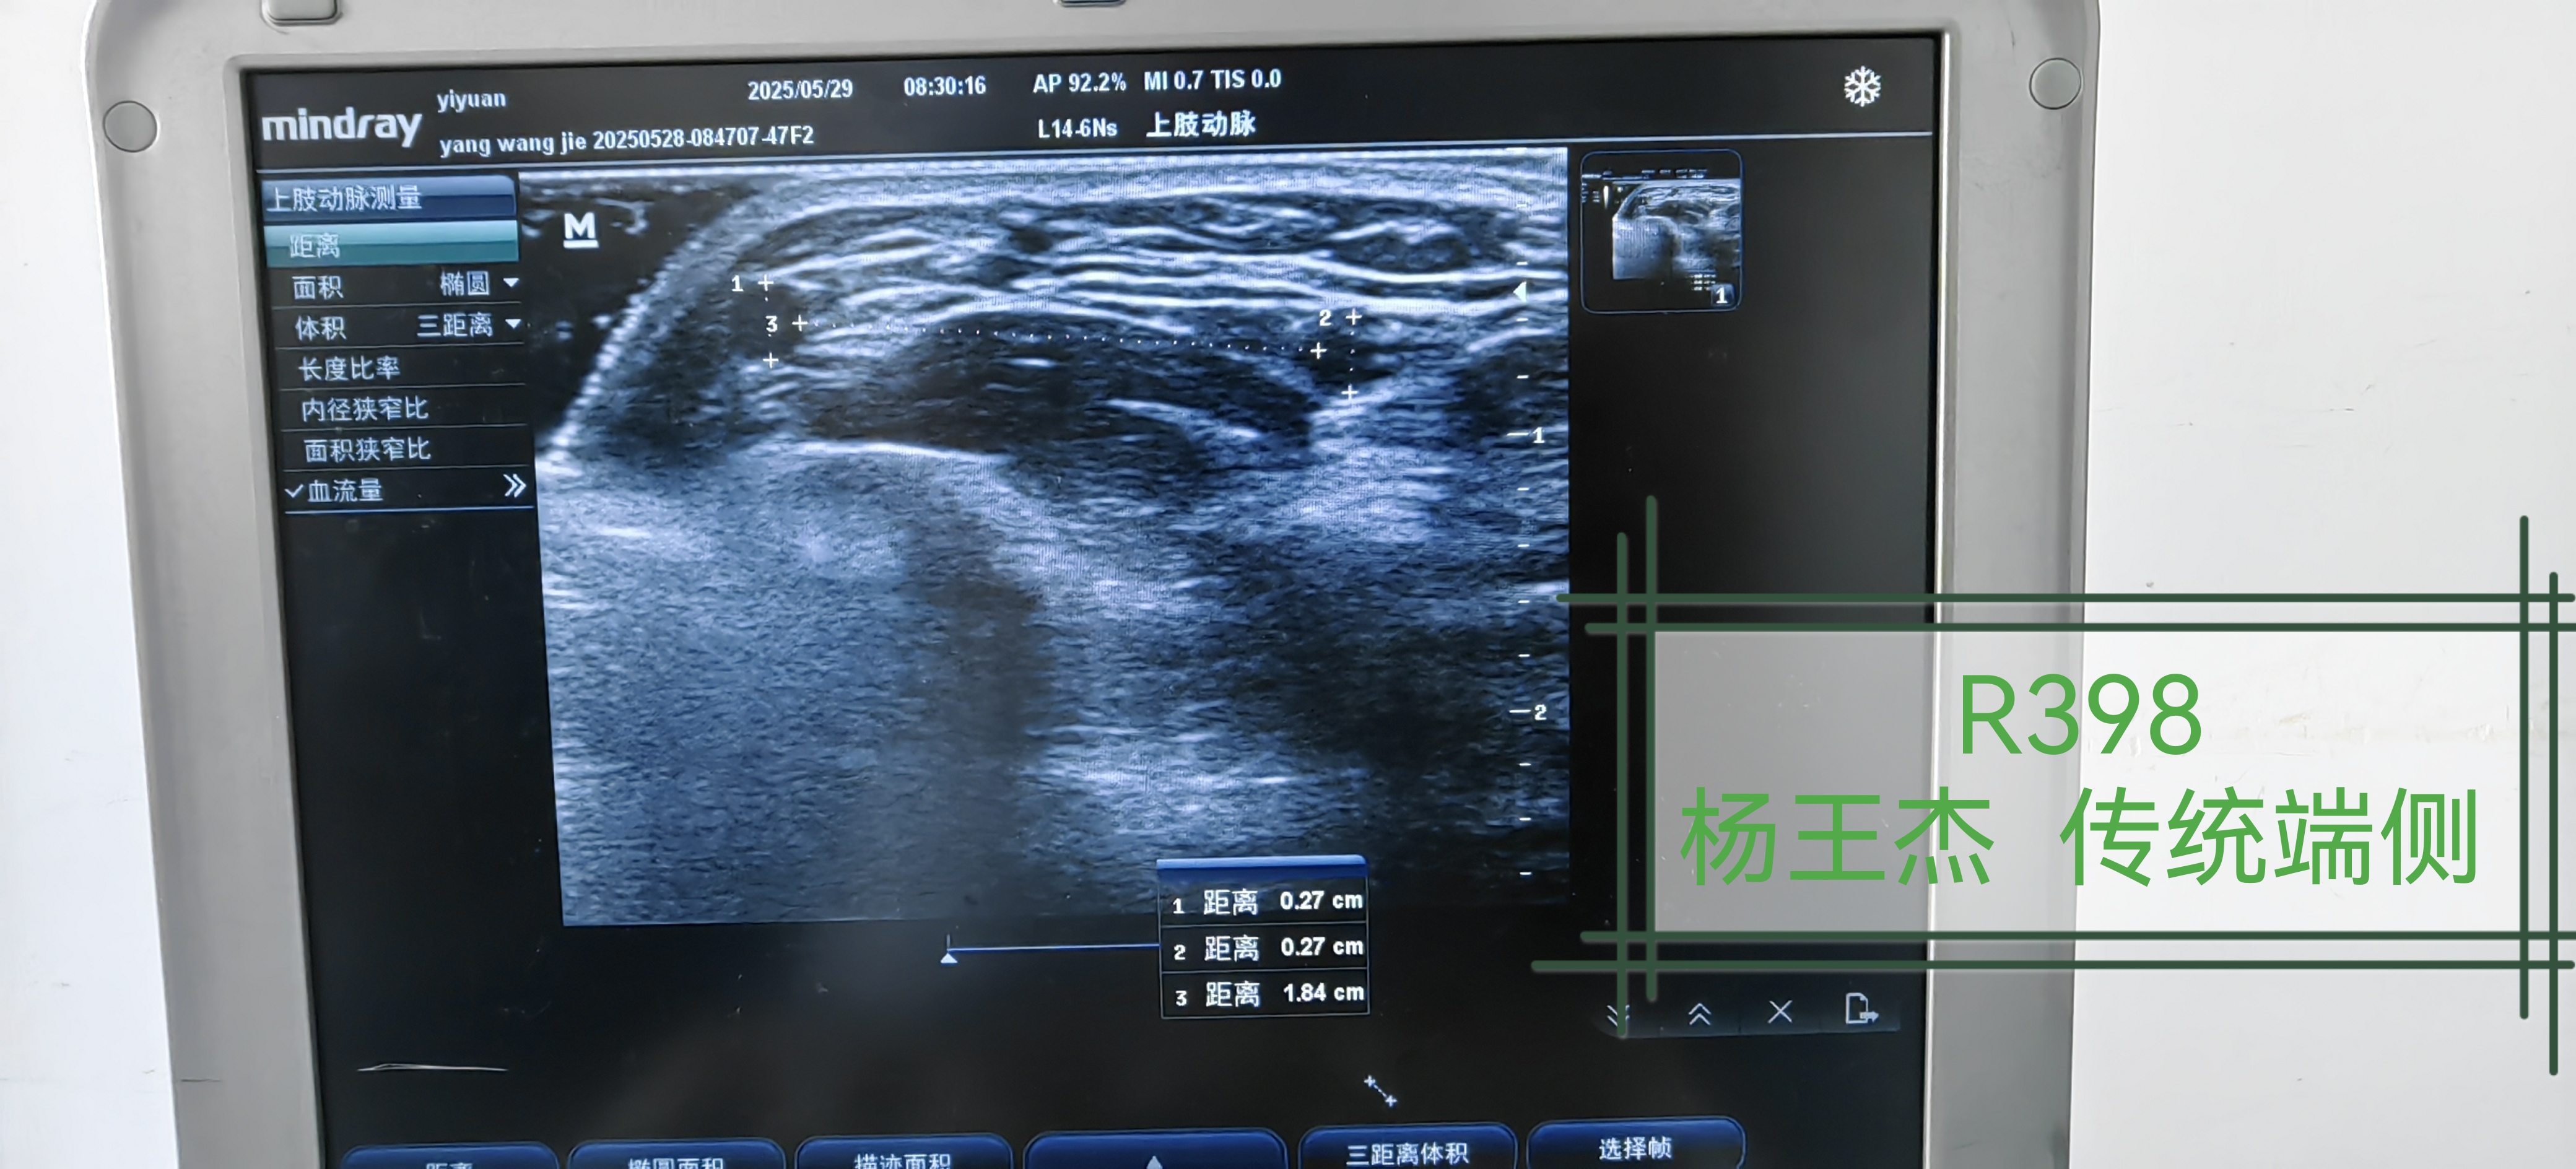

US results | /uploads/patrecord/11788/param512726/77ce1d96-db70-488b-b183-8d59128b602f.jpg |